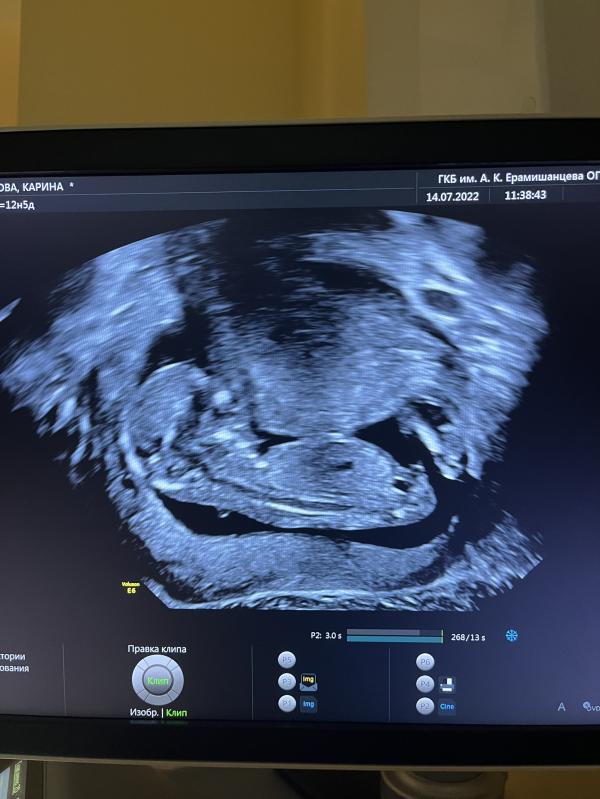

Но месячным (так настаивала врач) срок 12,4- идеально для скрининга.

По факту -сегодня ровно 14 недель , узить сказал - ещё бы один день и усе) неинформативно

Мне ни слова про тонус не сказали) сказали по узи все хорошо. Ребёнок лежит вниз головой. Изображение повернуто.